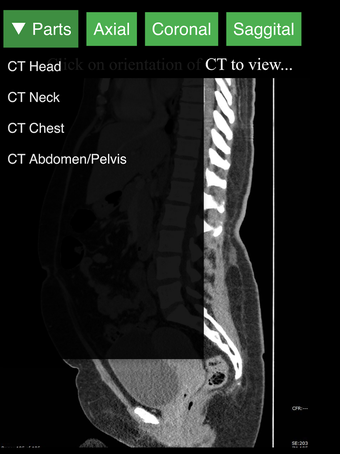

Radyoloji BT Görüntüleyicisi, doktorlar, tıp öğrencileri, radyoloji teknisyenleri ve diğer sağlık profesyonellerinin insan vücudu ve anatomisi hakkında daha fazla bilgi edinmelerine yardımcı olan faydalı bir araçtır. Uygulama, en önemli insan vücut parçalarının detaylı kesit çizimlerini içerir. Ayrıca, anatomiyi daha iyi görmek için görüntü etrafında döndürme, yakınlaştırma ve kamera hareket ettirme imkanı sunan etkileşimli bir 3D model içerir.

İnsan vücudu hakkında daha fazla bilgi edinmenize yardımcı olacak bir araç arıyorsanız, Radyoloji BT Görüntüleyicisi harika bir seçimdir. Detaylı çizimler ve etkileşimli bir 3D model içerir.